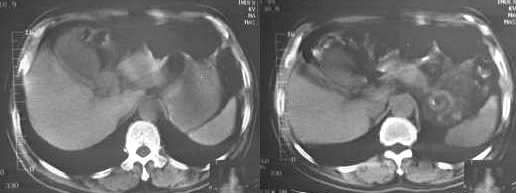

男,60岁,反复头痛,头昏,测血压最高240/120

临床怀疑嗜镉细胞瘤。做ct想了解肾上腺有无肿块。

疑问:1. 1185 1186 图 肝脏前缘低密度灶是否为腹水?ct值为-22——9.6

胆囊旁、肝脏前缘为运动伪影。胃内后方考虑肠管,建议此类检查前喝0.7%泛影葡安800ml后再扫描。